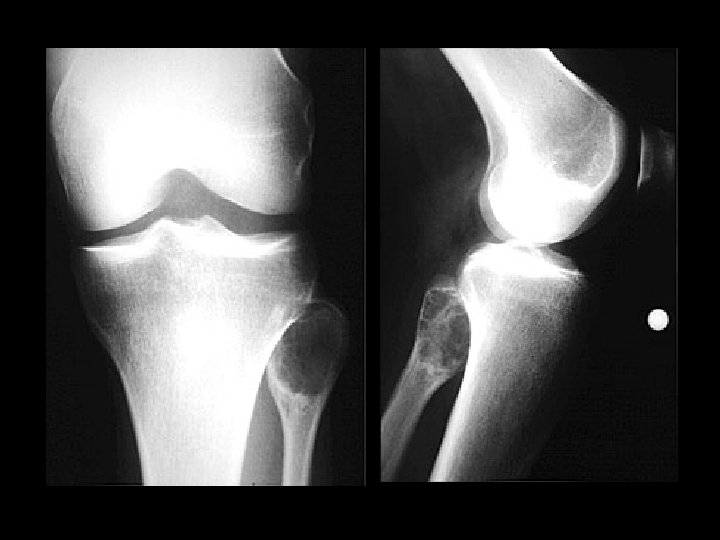

Pellegrini-Stieda disease • • Findings: – Linear ossific density adjacent to the medial femoral condyle Calcification or ossification of the MCL at its insertion site Sequela of previous injury NOT acute, usually not the site of pain